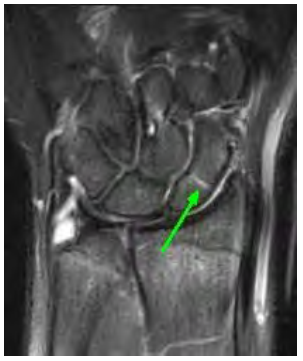

Uma paciente de 32 anos de idade sofreu queda sobre a mão espalmada. Após exame físico, foi realizado o exame de imagem apresentado.

A respeito desse caso clínico e da fratura indicada na imagem, assinale a alternativa correta.